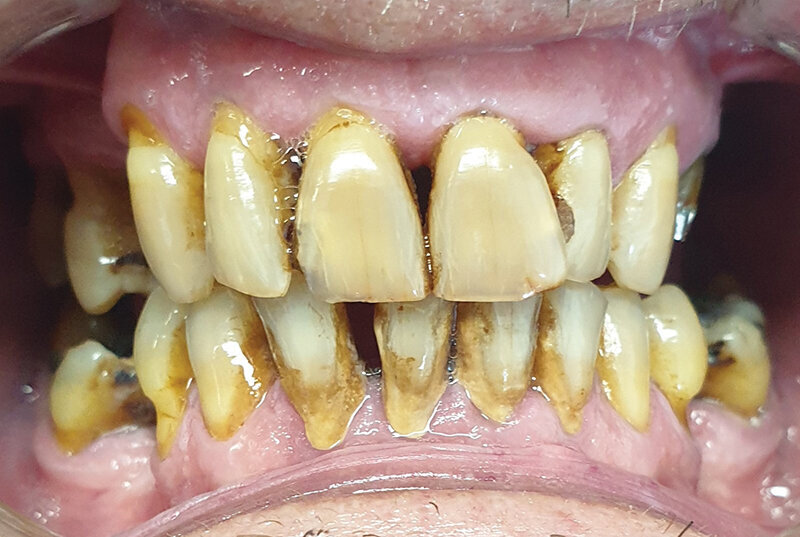

Pacijent A pušač pri prijemu. Jasno se uočavaju naslage u vidu estetski neprihvatljivih pušačkih pigmentacija na svim površinama zuba. Nizak nivo oralne higijene ogleda se u nalazu zubnog kamenca i visokom Plak indexu. Jasno su uočljive pušačke melanoze vidljivog dela desni kao i suvoća i beličaste promene obraznog dela sluzokože. Obložen jezik takođe je karakterističan nalaz višegodišnjeg pušača (Sl. 1.0).

Sl. 1.0: Pacijent A, pušač pri prijemu